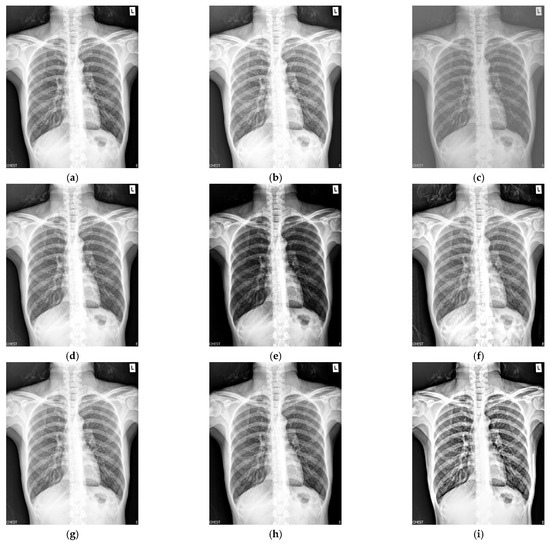

Figure 3 shows the enhancement images of eight approaches experimented on X-ray image 3. Figure 3a shows the original X-ray image 3; Figure 3b shows the enhancement result computed by McCann—the image is too bright, resulting in the loss of image details; Figure 3c shows the image achieved by RLBHE—the image is too dark, the useful information is lost; Figure 3d depicts the result achieved by RESIHE—the effect of enhancement is not obvious; Figure 3e shows the image obtained by TBCSSR—the image becomes gray and it is difficult to observe the details; the results enhanced by GDGIF, SMIPC, and FuzzyII are shown in Figure 3f–h, respectively. They are very similar and the enhancement effect is not prominent. Our method is depicted in Figure 3i—it performs well, and more details are retained. Table 3 shows the evaluation index values of the methods in Figure 3. Our method obtains the best values for all the metrics.

Figure 3.

Comparison on X-ray image 3. (a) Original image; (b) McCann; (c) RLBHE; (d) RESIHE; (e) TBCSSR; (f) GDGIF; (g) SMIPC; (h) FuzzyII; (i) Proposed method.

Table 3.

The metric data of eight methods on X-ray image 3.